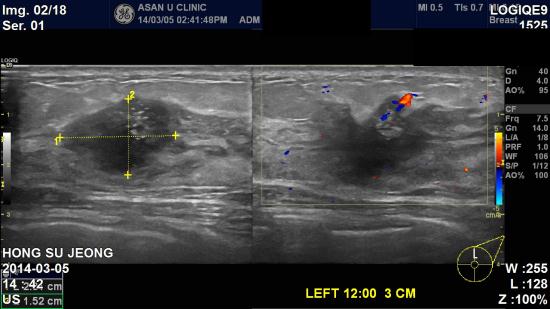

건강검진에서 실시한 유방암 검사상

좌측유방의 이상소견으로 내원하신 34세여자분이십니다.

본원 초음파상 좌측유방 12시방향에 2.31 cm 의 결절과,

좌측겨드랑이 림프절 비대소견있어